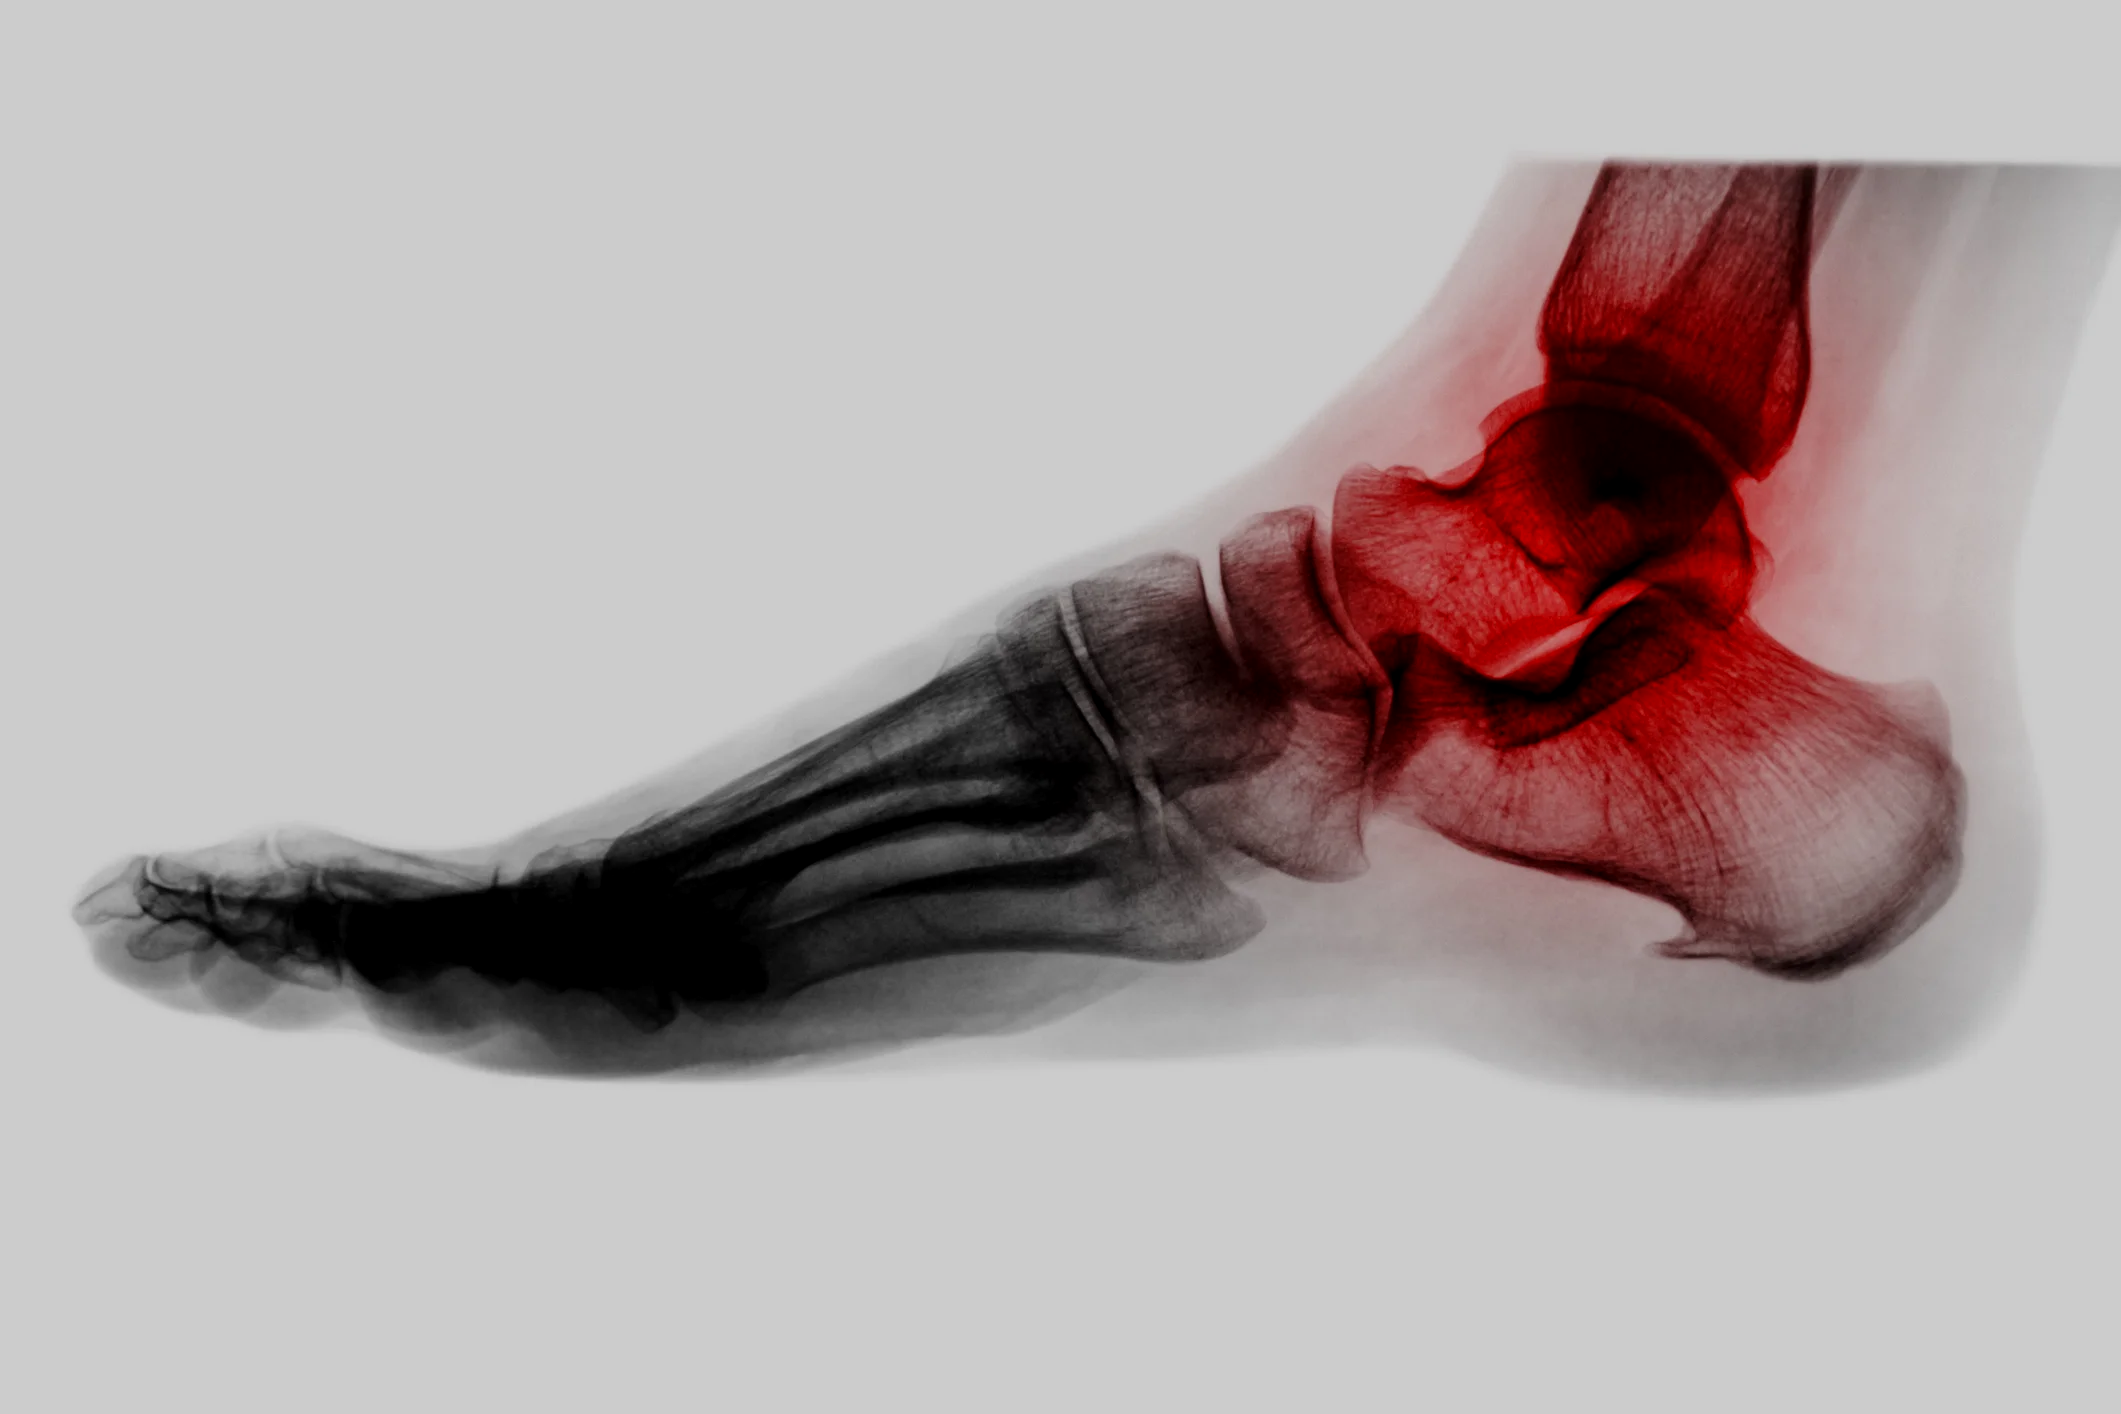

Ankle/Hindfoot Conditions

There are many conditions that can affect the ankle or hindfoot. Sometimes these are tendon problems but can also include ligaments, joints and other soft tissue structures.